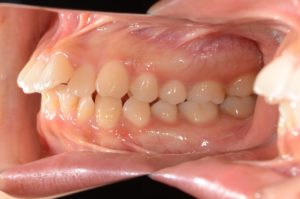

【スプリント治療後】

歯並びは変わっていませんが、顎の位置が正常に安定したことで

噛み合わせの位置が変化していることが分かります。

正しい位置で咬めるようになったためインビザラインに移行します。

【インビザラインにて動的治療スタート】

約2年6ヵ月、インビザラインによる非抜歯での動的治療。

【動的治療終了時】

スプリントの期間も合わせると約3年で歯並び、噛み合わせともにしっかり整いました。

この状態がキープできるようリテーナー(保定装置)に切り替え、保定期間に入ります。